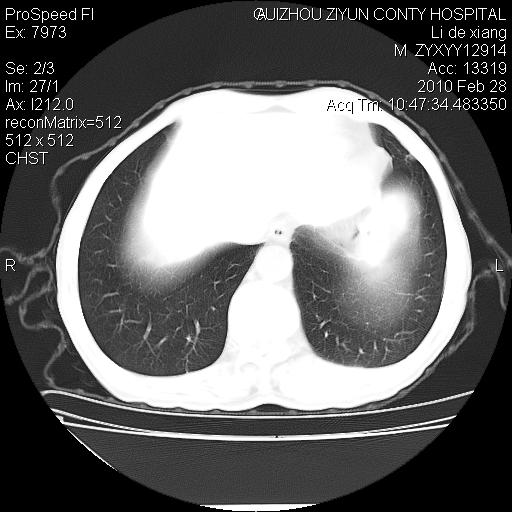

标题: CT24776:男 71Y 咳嗽咳痰胸痛两月,伴声音嘶哑。 [打印本页]

标题: CT24776:男 71Y 咳嗽咳痰胸痛两月,伴声音嘶哑。

左侧中央型肺癌伴左肺上叶阻塞性肺炎及节段性不张可能性大,建议纤支镜检查!

左侧中央型肺癌伴左肺上叶阻塞性肺炎及节段性不张可能性大,建议纤支镜检查!纵隔淋巴结转移.

左侧中央型肺癌伴左肺上叶阻塞性肺炎及纵隔淋巴结转移。

左肺门部肿块,伴左上肺斑块影,周边模糊,支持左肺中央型肺癌伴节段性不张及阻塞性肺炎,结合支气管镜检查。

左上叶支气管狭窄,阻塞性病变,肺门肿块,纵隔及肺门淋巴结增大,中央性肺癌

左肺中央型肺癌并阻塞性改变、纵膈 淋巴结转移

左侧中央型肺癌伴左肺上叶阻塞性肺炎及纵隔淋巴结转移